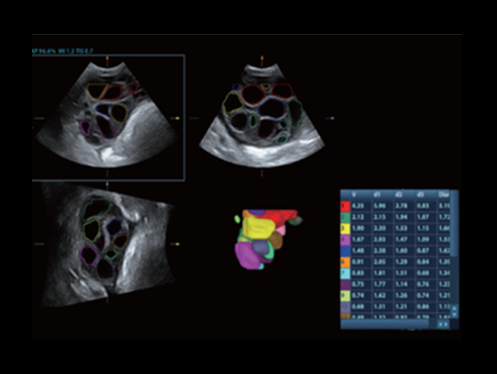

W aparacie DC-80A X-Insight zintegrowano inteligentne rozwi?zania z profesjonalnymi narz?dziami diagnostycznymi w ró?nych aplikacjach i podczas ca?ego cyklu badań: od pocz?tku ci??y, poprzez badania prenatalne, a? po opiek? poporodow?.

Obrazy kliniczne